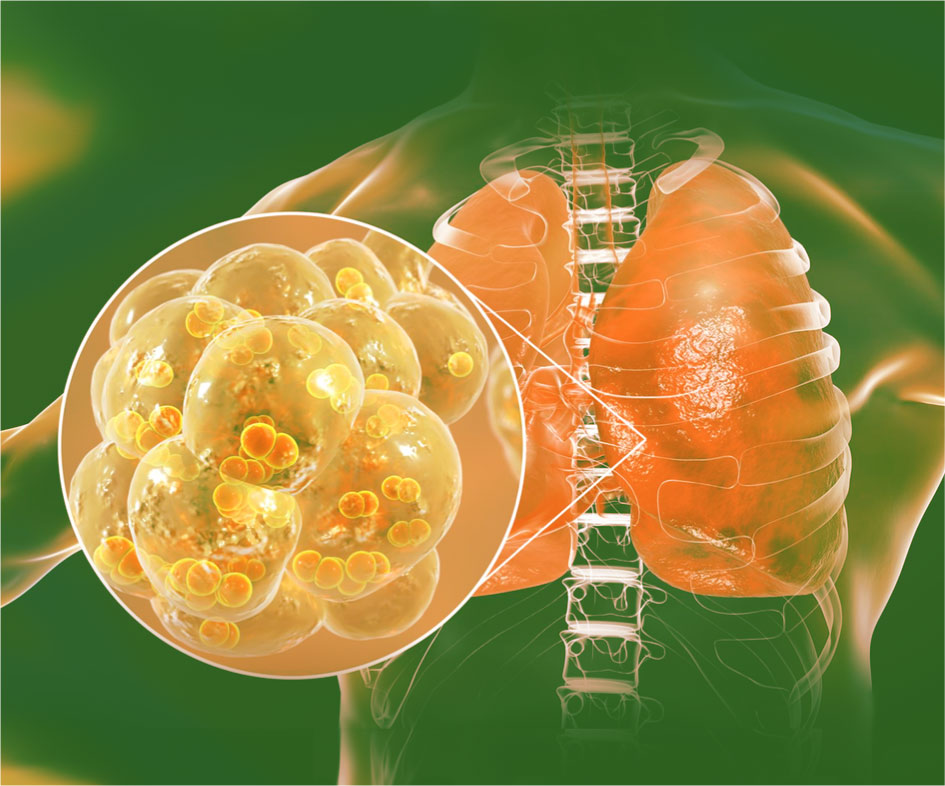

Пневмококковая инфекция: полное руководство по защите, диагностике и лечению

Столкнулись с риском заражения или уже боретесь с болезнью? Эта статья поможет разобраться в причинах, симптомах и формах пневмококковой инфекции, а также подробно расскажет о современных методах лечения…